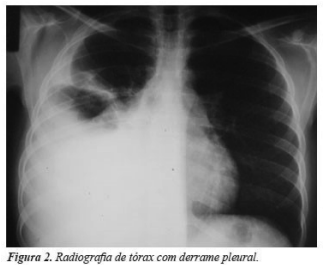

Realizou RX de tórax, conforme figura abaixo. Considerando a

principal suspeita clínica, deveria ser solicitado, na análise do

líquido pleural para melhor elucidação diagnóstica, a: